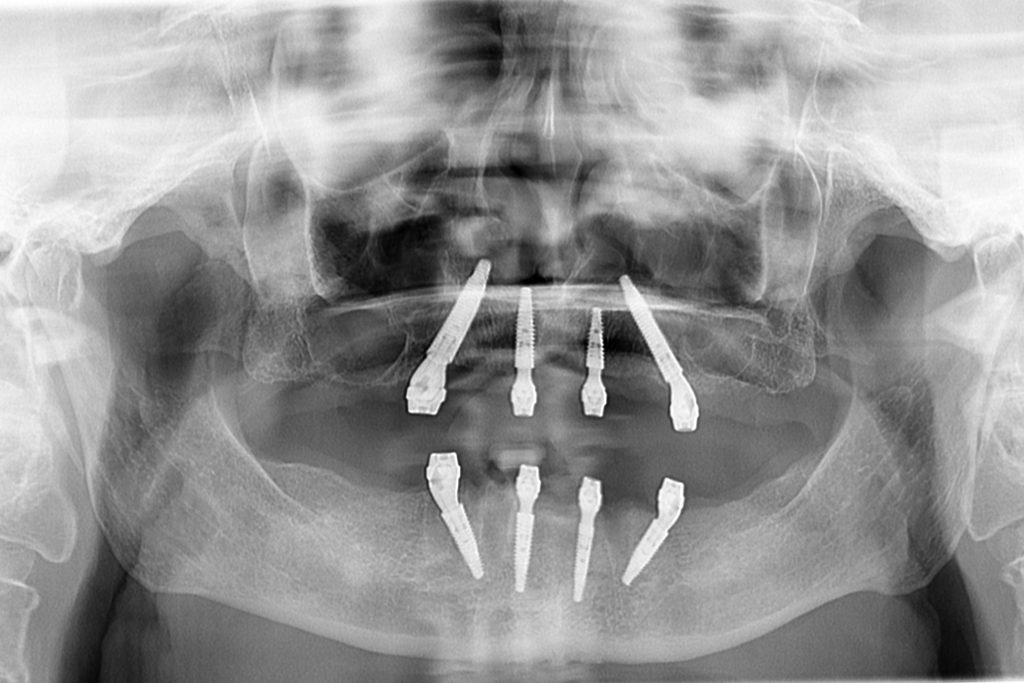

Dr. Vladimir Malušev is a Specialist in Oral Surgery (University of Belgrade) and an active member of the International Team for Implantology (ITI). He is a cofounder and lead clinician at White Clinic Belgrade. With a passion for Graft Free Implantology, he is dedicated to providing patients with minimally invasive dental solutions.